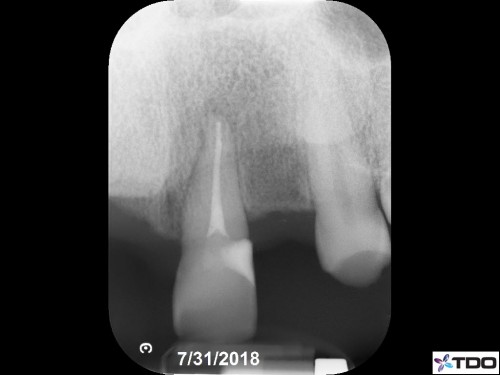

47 yof. Symptomatic partially necrotic pulp. First visit instrumented with #15K to length. Second visit apically gauged to a size 40.